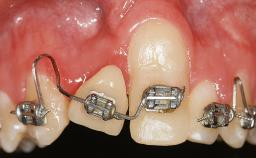

In 1983, a 51-year-old non-smoking patient was referred for the treatment of moderate chronic periodontitis. At the initial examination, 47% of sites exhibited probing depths of 4 to 6 mm. Periodontal therapy consisted of initial periodontal treatment including oral-hygiene instructions and supra- and subgingival debridement, followed by periodontal surgery to eliminate residual pockets.

Periodontal Status History of periodontitis or genetic predisposition